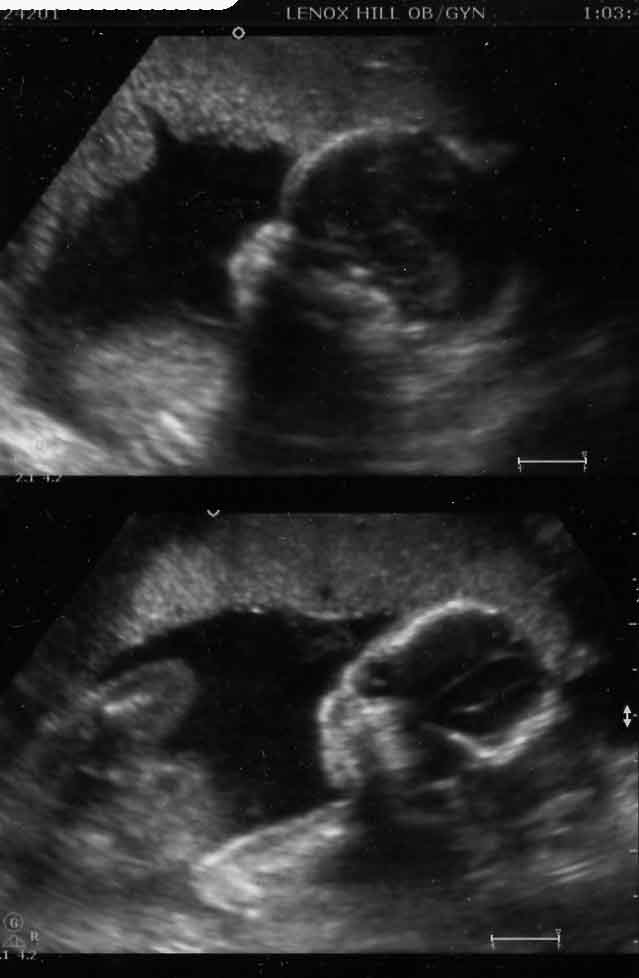

10 week sono today (PICS)

Just wanted to share a pic from my 10 week sono. I cant believe how much has changed since wk 6. At 6 weeks it was literally a dot, I had no idea I would be able to actually see this much today. It was so incredible bc at one pt the baby started "dancing"...DH and I couldnt stop crying...

Top pic is @ 10 wks Bottom pic is @ 6 wks